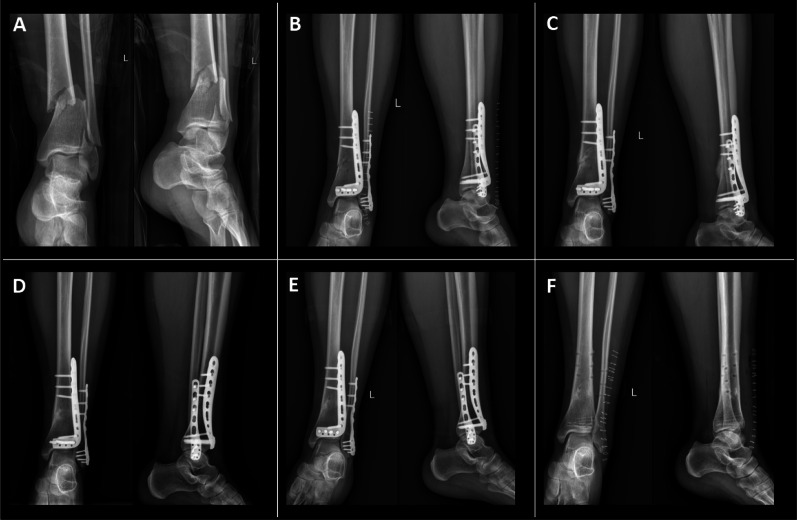

Background: Current literature on ultra-distal tibial fractures (UDTF) is relatively limited, particularly regarding the outcomes and complications of different treatment strategies, with data being notably scarce. This study aimed to compare the clinical outcomes of intramedullary nailing (IMN) and distal tibial plate (DTP) fixation in the treatment of UDTF.

Methods: A total of 48 eligible patients were retrospectively reviewed and divided into two matched groups based on age, gender, injury severity score, and fracture type. The IMN group comprised 21 patients, and the DTP group included 27 patients. All patients were followed up to assess both clinical and radiological outcomes.

Results: The IMN group demonstrated significantly shorter surgery time (P = 0.043) and fracture healing time (P = 0.002) compared with the DTP group. However, no significant differences were found between the two groups in terms of time from fracture to admission (P = 0.740), preoperative hospital stay (P = 0.310), postoperative hospital stay (P = 0.379), infection rates (P = 1.000), or rates of nonunion (P = 0.822). Postoperative malalignment occurred in three patients in the IMN group and one patient in the DTP group (P = 0.430). The mean postoperative angulation in both groups was similar in the coronal plane (P = 0.101) and sagittal plane (P = 0.334). The mean Olerud-Molander Ankle Score (OMAS) was 88.62 ± 5.24 in the IMN group and 85.85 ± 8.39 in the DTP group (P = 0.169).

Conclusion: Both implants are effective in treating UDTF. However, IMN offers advantages in reducing surgical time, accelerating fracture healing, and promoting early recovery. Therefore, IMN may represent a superior surgical option for managing UDTF.